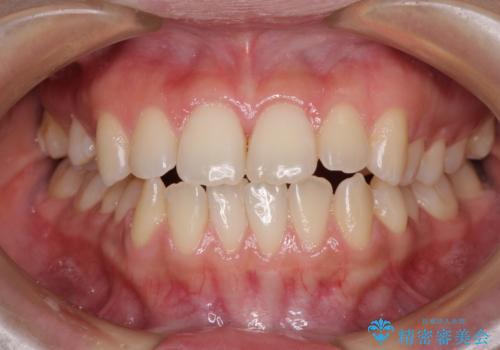

- 上下のデコボコと奥歯の咬みにくさを気にして来院された患者様です。

上顎骨の幅が下顎骨よりも小さく受け口傾向であったため、拡大装置により上顎骨の骨幅を広げて上下関係を改善し、その後インビザラインにて歯並びを整えることとしました。